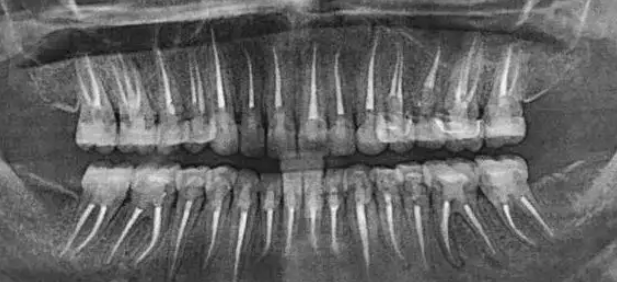

根管不做冠,早晚是后患!患者“不做冠”后牙齿劈成了两半!